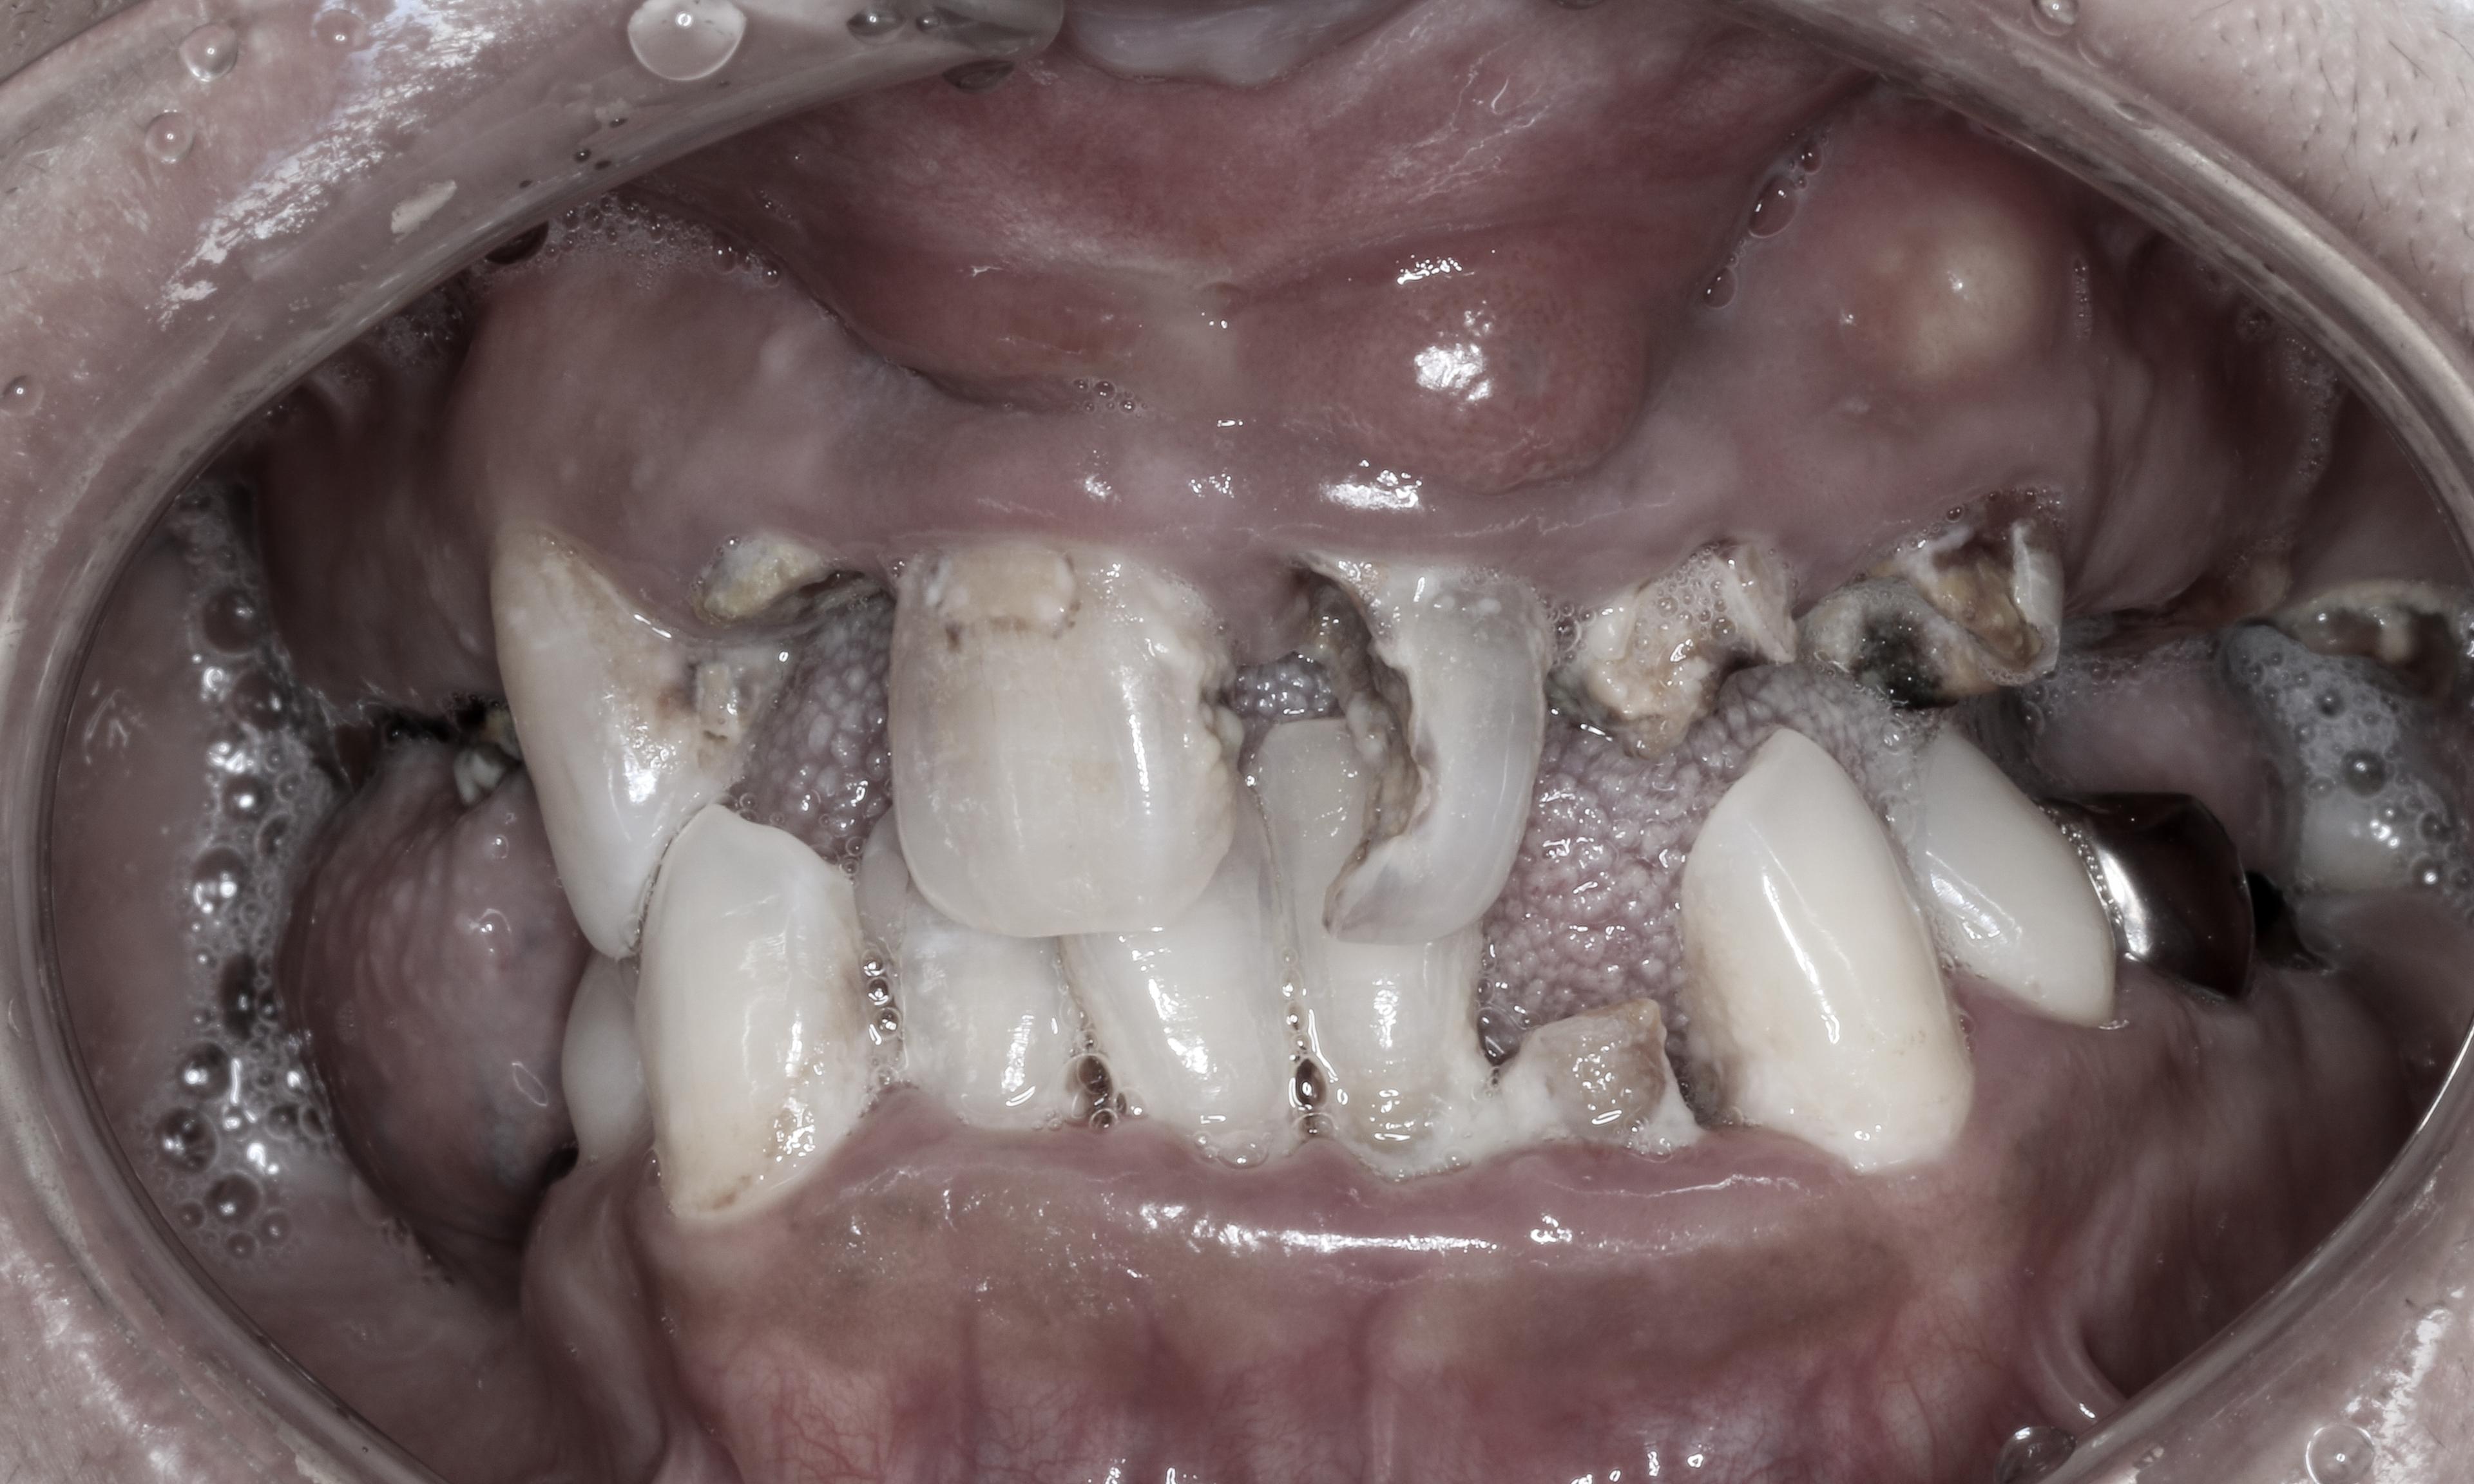

大病を患っていたことから口腔ケアが出来ず重度歯周病と歯冠崩壊が進んでしまったケースです。矯正治療とインプラント治療を組み合わせ、可能な限り天然歯を保存して口腔再建を行いました。